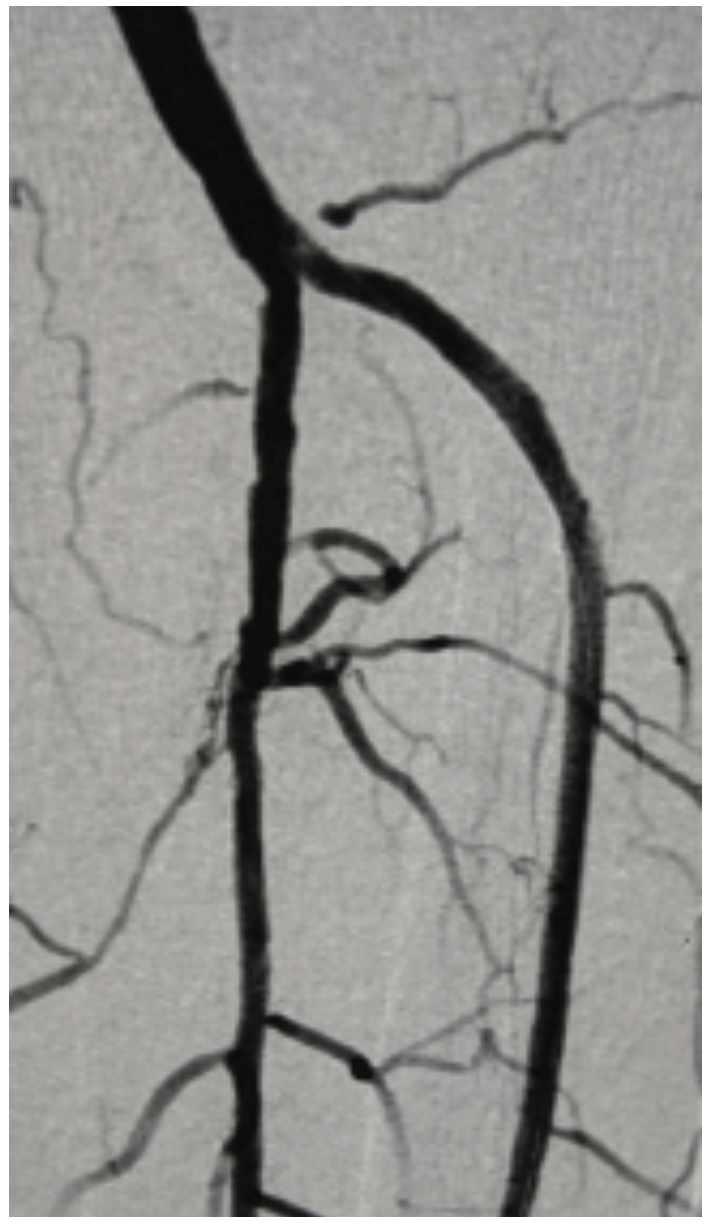

This is a 71-year-old male with a prior history of aortic valve replacement on coumadin, peripheral arterial disease, myocardial infarction, diabetes, and chronic kidney disease. He presented with a 3-month history of ischemic rest pain involving the left lower extremity, no wounds. He had previously undergone left superficial femoral artery (SFA) stenting for a chronic occlusion, but despite this, continued to have rest pain with peroneal-only runoff (Figures 1-4). He was brought in for left anterior tibial artery recanalization.

The patient qualified for the MicroMedical MicroStent trial, and both antegrade left lower extremity and retrograde dorsalis pedis access were obtained. The TASC II type D lesion of the anterior tibial artery origin was crossed with a V-18 wire (Boston Scientific), from below, and the wire was externalized via the antegrade sheath. Additionally, an .014-inch wire and balloon were placed into the tibioperoneal trunk and a 3 mm balloon was inflated across the origin of the anterior tibial artery. This “SOBE balloon protection technique” was used both to mark the origin of the anterior artery as well as serve as a buttress for placement of the stent (Figure 5). A 3 mm x 40 mm MicroStent was chosen and advanced through the 3 French (Fr) sheath from the dorsalis pedis access to the anterior tibial artery origin. The stent was placed across the lesion with precision to the origin. A 3 mm balloon was then inserted through the portal access and the stent was dilated to profile. Then the tibioperoneal trunk balloon was deflated and completion angiography was performed. Inline flow had now been created to the foot via the peroneal and anterior tibial arteries (Figure 6).